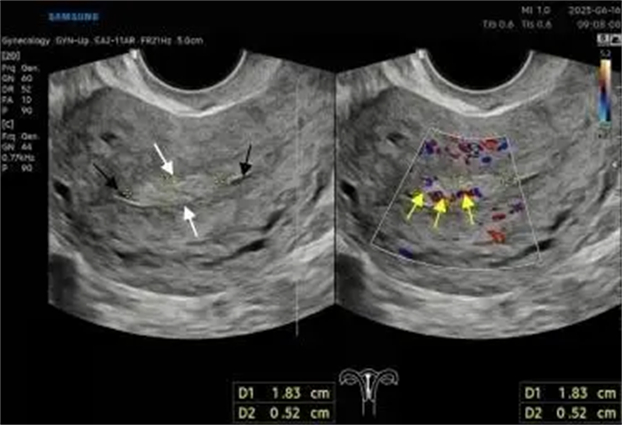

“无脉症”?颈脑血管超声联合检查,揪出血管的“窃血贼”——超...